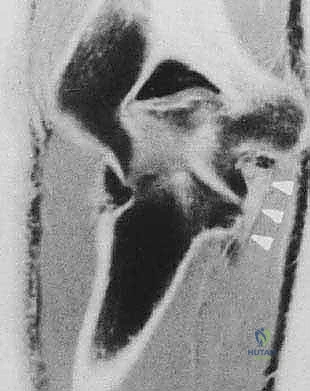

* الأشعة السينية (X-rays): ضرورية جداً لرؤية النتوءات العظمية (Osteophytes) في الناتئ المرفقي، وتضييق مساحة المفصل.

* التصوير بالرنين المغناطيسي (MRI): يُستخدم لتقييم الأنسجة الرخوة، وتحديداً حالة الرباط الجانبي الزندي (UCL)، والكشف عن وذمة نخاع العظم (Bone Marrow Edema) الناتجة عن الاصطدام المتكرر، وتقييم حالة الغضاريف.

* الأشعة المقطعية (CT Scan): في بعض الحالات المعقدة، تُستخدم لبناء نموذج ثلاثي الأبعاد للمفصل للتخطيط الجراحي الدقيق قبل إدخال المنظار.